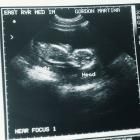

Die Anzahl der Ultraschalluntersuchungen(normalerweise sind 3 Untersuchungen vorgesehen) wird sich erhöhen. Bis zur 16. Schwangerschaftswoche wird geprüft wie die Eihäute angelegt sind, um zu klären ob es sich um ein - oder zweieiige Zwillinge handelt. Später wird sowohl das Wachstum der Kinder, als auch die Anlage der Organe untersucht. Vorsorgeuntersuchungen werden etwa doppelt so häufig durchgeführt als bei Einlingsschwangerschaften.